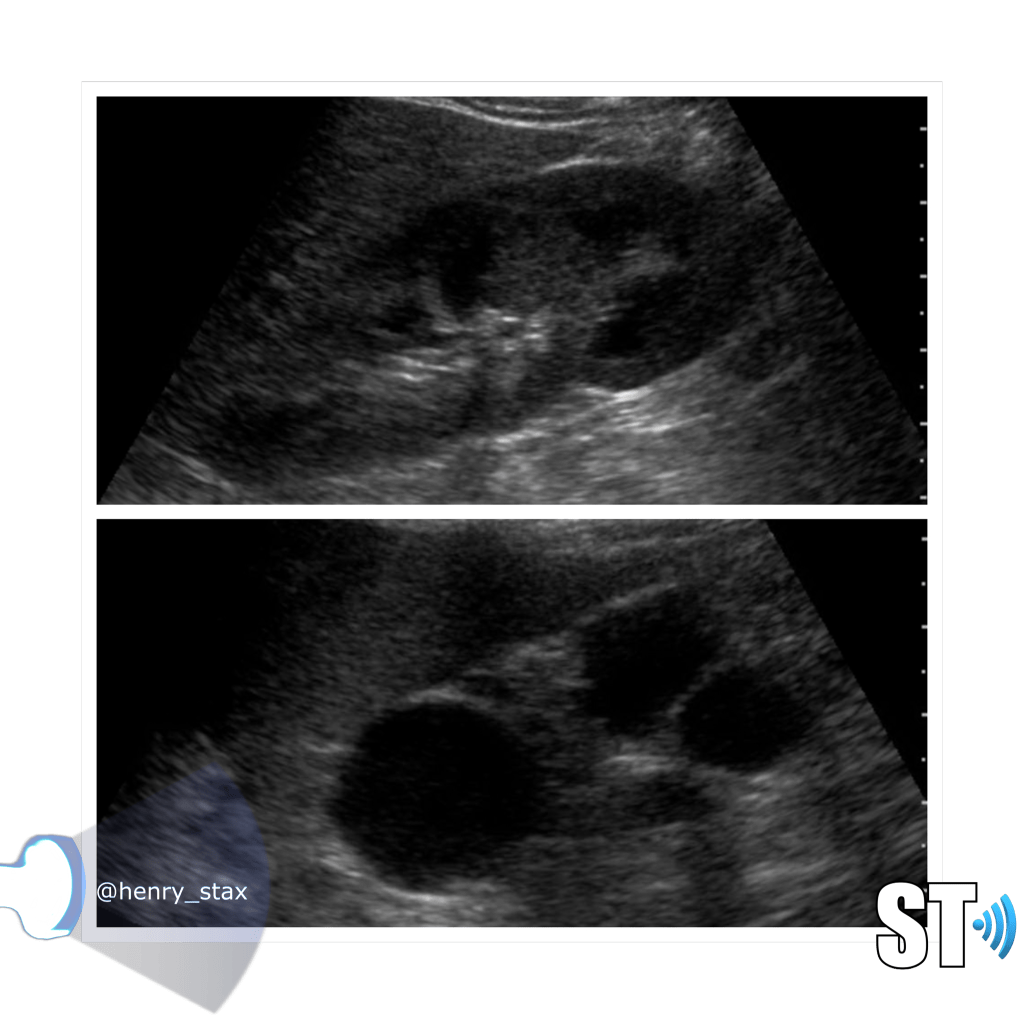

ADPKD

In Autosomal Dominant Polycystic Kidney Disease (ADPKD) the kidneys are normal at birth with cysts developing overtime. By age 30 years, approximately 68% of patients will have visible cysts by ultrasound. Eventually, virtually all patients develop cysts. The disease is transmitted in an autosomal dominant pattern, meaning you only one abnormal gene from one parent.

One abnormal gene from one parent

- Adult

- 4-10% of all cases of ESRF

- Kidneys appear normal early on

- Liver, pancreas and spleen cysts